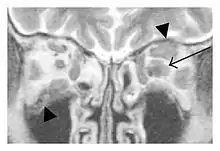

Infraorbital nerve enlargement (IONE) is considered to be a particularly suspicious sign of IgG4-ROD, but seems to occur only when inflammation is in direct contact with the infraorbital canal.[10] IONE is defined as the infraorbital nerve diameter being greater than the optic nerve diameter in the coronal plane.

![]() Swelling of the left superior and lateral rectus muscles, a mass lesion around the left optic disc (arrow), and enlargements of the left supraorbital nerve and the right infraorbital nerve (arrow heads) in a 60-year-old man with a serum IgG4 of 463 mg/dL.[1] (T1-weighted MRI) |